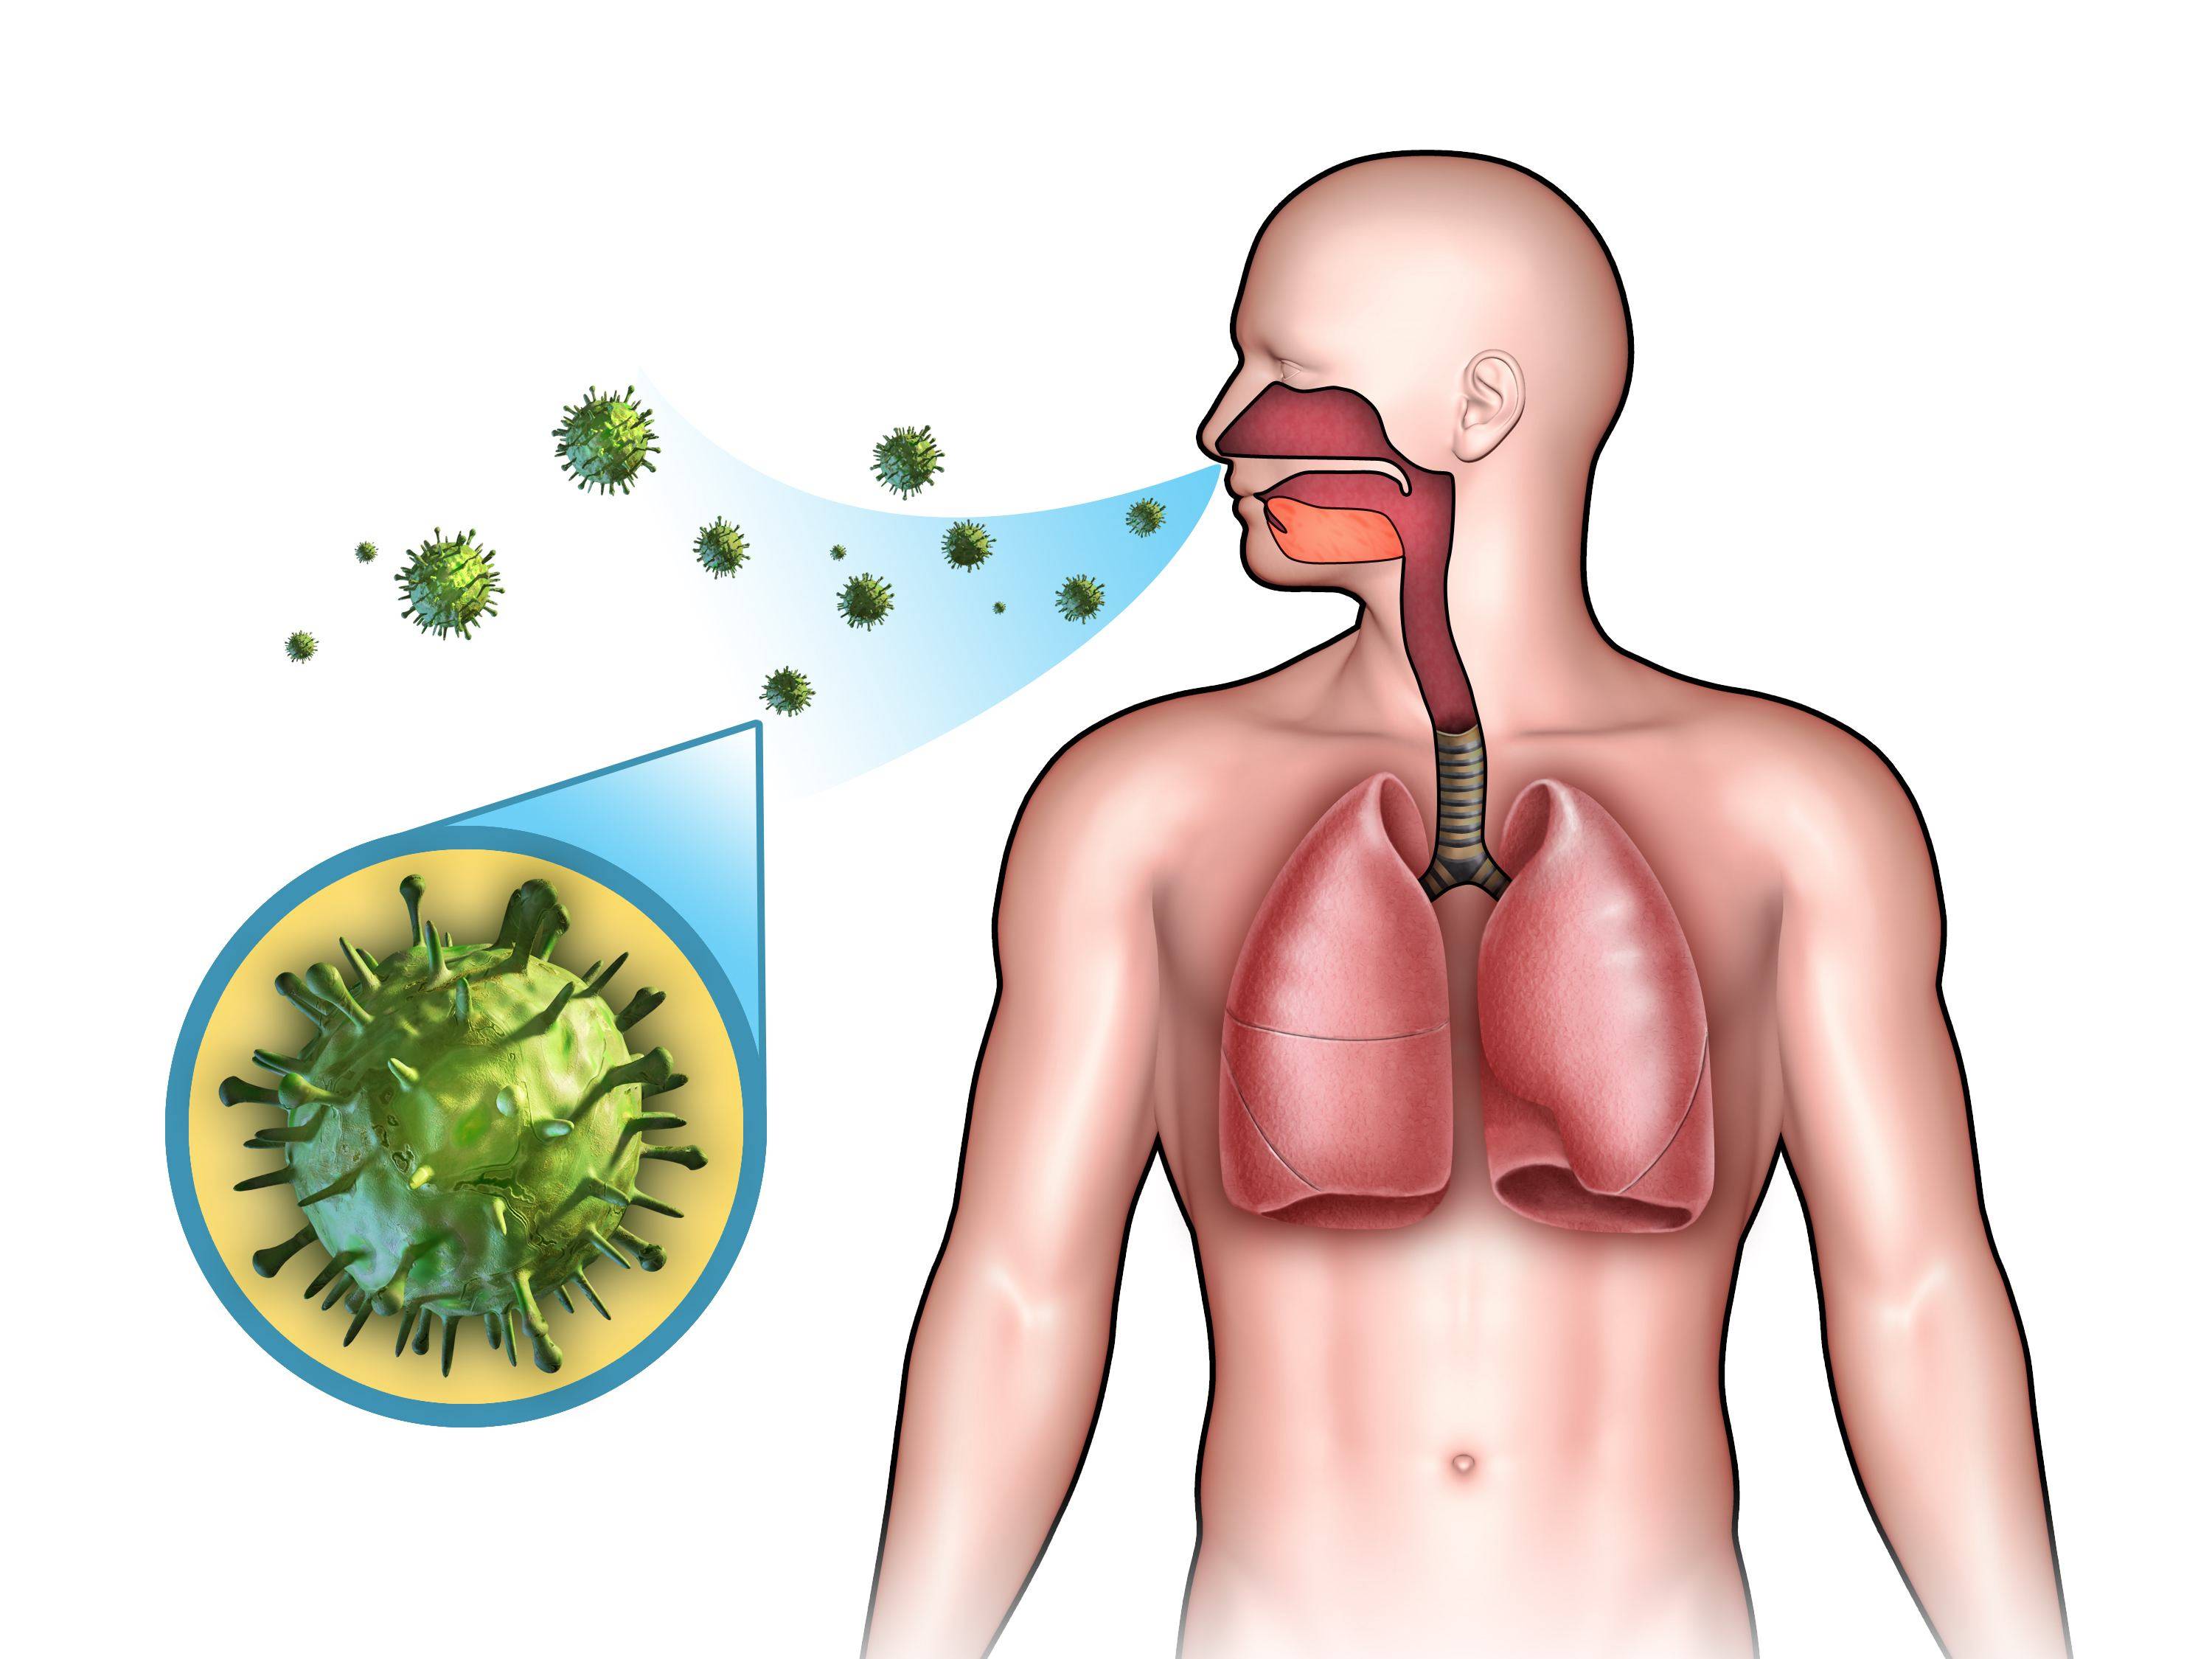

Современные методы лечения туберкулеза